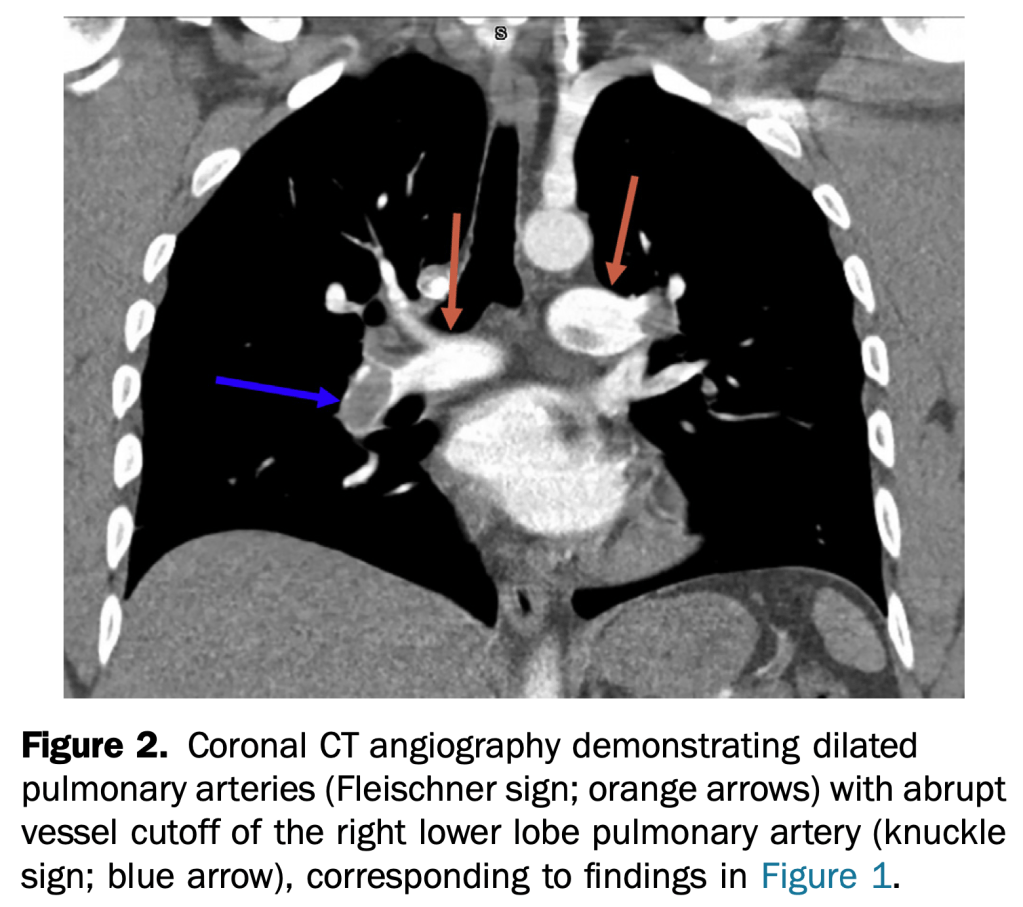

- An otherwise healthy 35-year-old active duty military infantryman presented to the emergency department, complaining of intermittent dyspnea over one-week duration, which was worsened by exertion. He recalled some unusual left leg cramping three weeks before and reported an uncomplicated tooth extraction one week before, but denied any invasive surgeries.

- This case demonstrates multiple rare but specific radiographic findings of pulmonary embolism. These include the Westermark, knuckle, and Fleischner signs, in addition to Hampton’s hump.